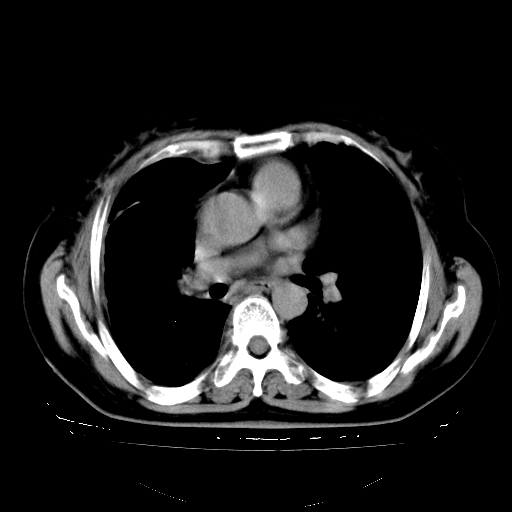

以下是引用zhangzhongshou在2008-3-22 12:52:00的发言:[br]1、右侧液气胸。[br]2、腹水。建议进一步检查。

以下是引用鲁巨ct在2008-3-22 14:10:00的发言:[br]1、右侧液气胸,右中下叶节段性不张。[br]2、腹水,建议上腹部ct检查

以下是引用zjzjr在2008-3-22 17:19:00的发言:[br]1、右侧液气胸,右下叶节段性不张。[br]2、腹水,建议上腹部ct检查